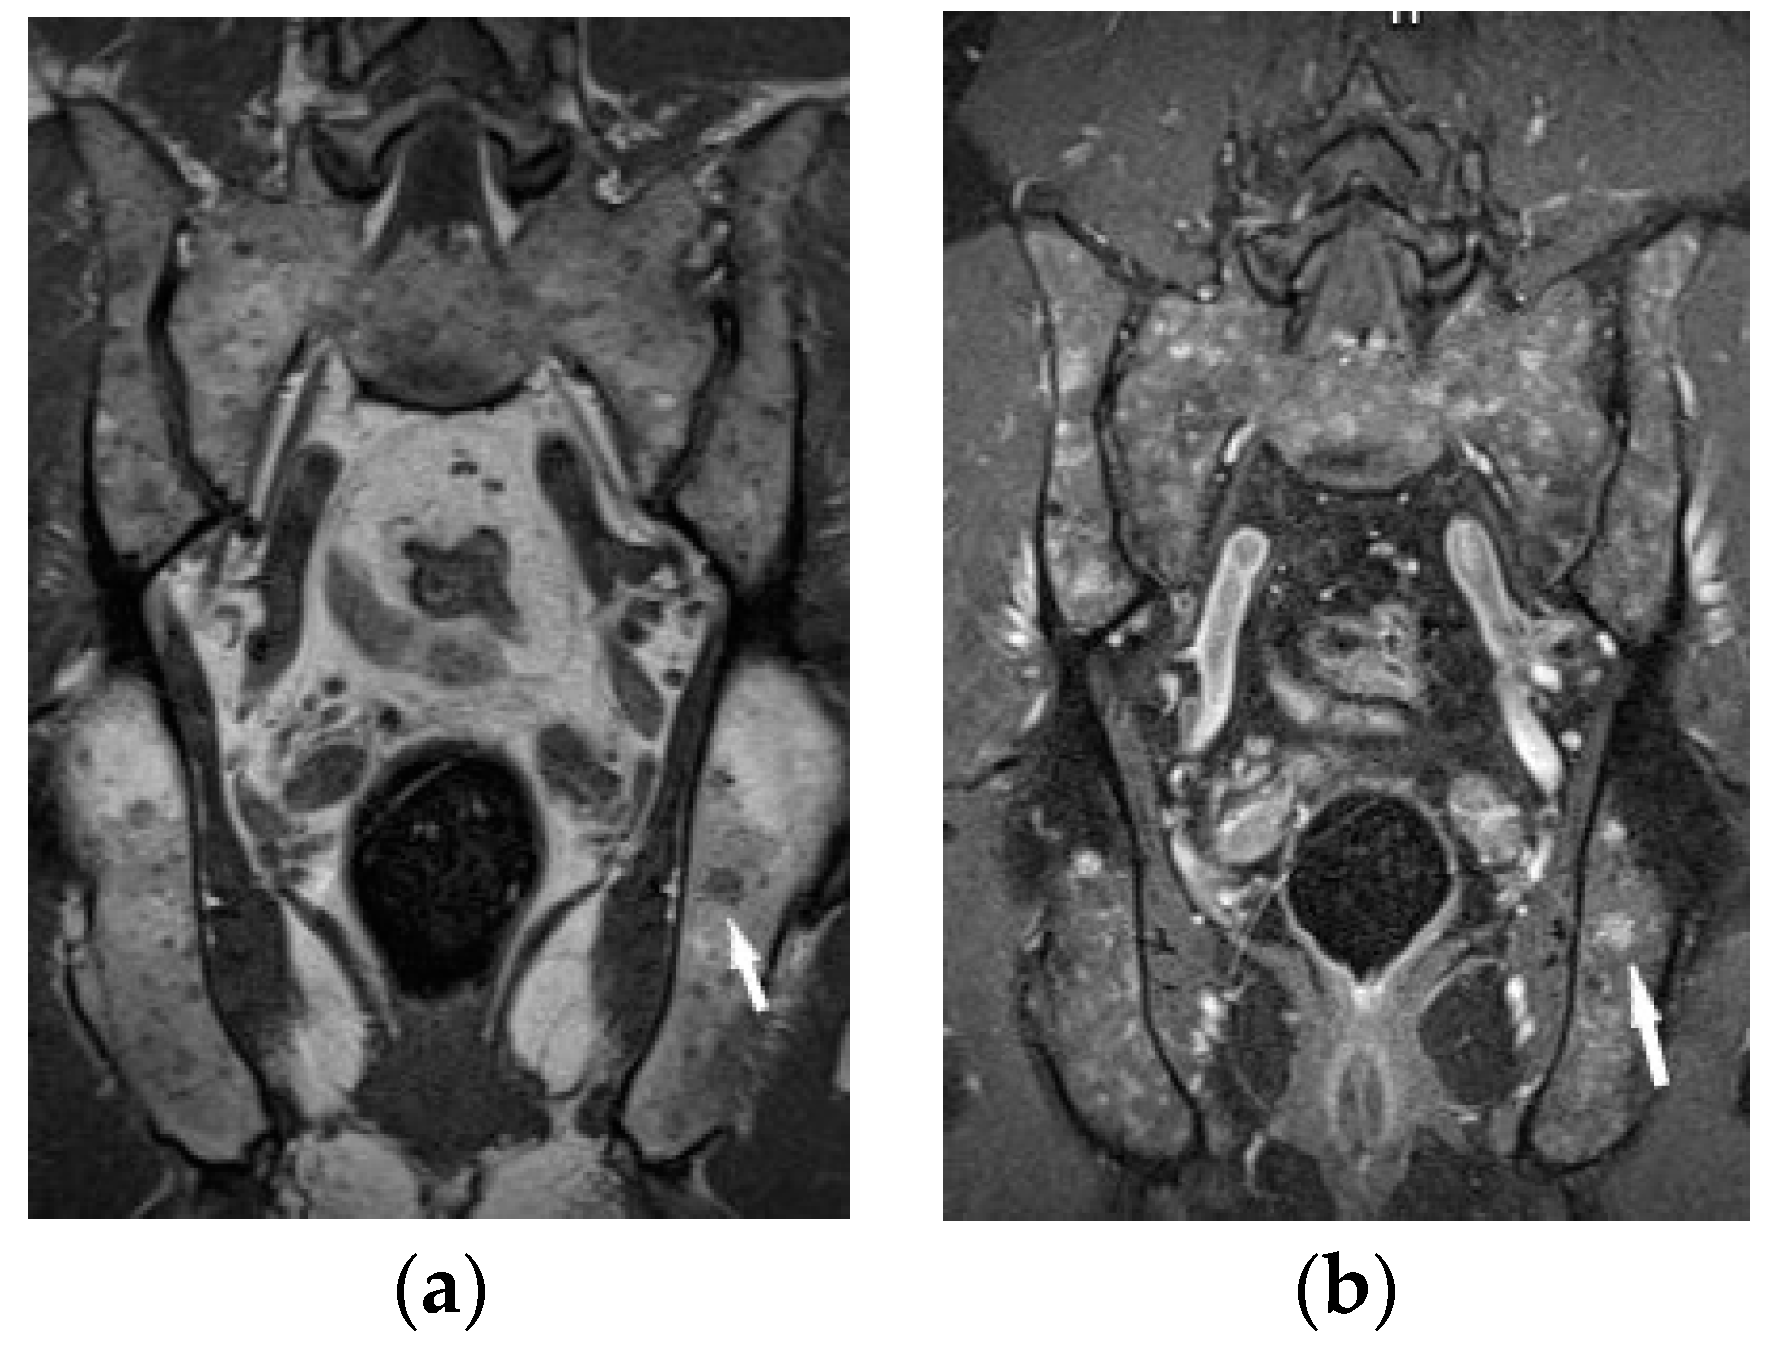

Chronic arthritis, either mono-articular or poly-articular, occurs in the later phases of the disease, usually as a part of a multisystem manifestation. In addition to synovitis (Figure 5a,b), erosions of the articular surfaces may be present, making it necessary to differentiate the lesions from reactive or rheumatoid arthritis [19]. An additional difficulty is that the rheumatoid factor may be positive in 10–47% of cases [20]. If differential diagnosis is necessary, a synovial US-guided biopsy is performed. Detection of granulomas in a synovial biopsy sample helps make the diagnosis of sarcoidosis [20]. X-ray shows soft tissue swelling and epiphyseal demineralization.

Long-lasting joint inflammation leads to the narrowing of the joint space. In the sarcoid arthritis diagnostic imaging, we mainly use X-ray, US, and MR imaging. MRI shows with high sensitivity the joint effusion and features of synovitis, cartilage destruction, and inflammatory changes of periarticular structures such as peritendinitis, tendinitis or bursitis (Figure 5a,b) [20].

The radiographic appearance of phalanges occupied by sarcoidosis includes lytic lesions of various sizes, called cysts. Cystic lesions, mostly punched-out, may be accompanied by soft tissue nodules. The presence of large cysts increase the risk of pathological bone fracture [20] (Figure 6a,b). Numerous small cysts are more frequently observed. The articular surfaces are preserved, although cysts located in the subchondral layer might mimic erosions (Figure 7). Periosteitis is uncommon.

Features of bony destruction may be permeative and cause scalloping of the cortex, whereby cortical margins are preserved. Bone destruction with moth-eaten pattern may involve the cortex, usually with associated soft tissue swelling [19]. The cortical and trabecular architecture is usually remodeled [20]. The phalanges of the second and third fingers of the hand are most often involved, leading to the image of sausage-shaped fingers [20].

Figure 5. Radiograph (a) and MRI of the elbow (b) performed in a 45-year-old woman with sarcoidosis. Osteolytic lesion in the proximal part of the elbow bone ((a), white arrow). T2-weighted image with fat saturation revealed a synovitis, erosion in the proximal part of the elbow bone corresponding to this bone lesion (black arrow) and slight bone marrow edema in the head and neck of the radius (asterisk).